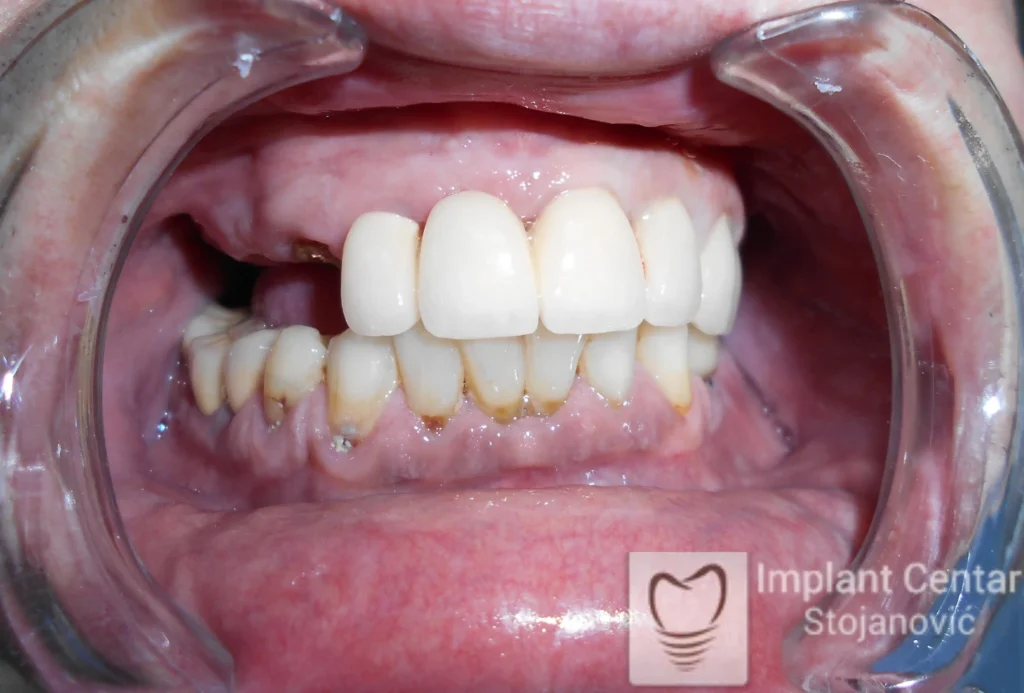

Na slikama 1, 2, 3 , 4  i  5 prikazan je izgled pacijenta pre početka terapije. Nakon detaljne kliničke i radiološke analize, doneta je odluka o vađenju zuba loše biološke vrednosti, dok su bezuba polja sanirana ugradnjom dentalnih implantata.

Nakon ugradnje implantata i pripreme preostalih zuba, pacijentu su izrađene fiksne privremene krunice, čime je postignut eugnatan zagriz već nakon jednog dana (slika 8, 9 i 10). Tokom perioda osteointegracije, pacijent se postepeno privikavao na novi položaj vilica i zagriz.

Po završetku perioda integracije, izrađeni su definitivni cirkonijum-keramički mostovi, čime je postignuta potpuna rekonstrukcija zagriza, kao i značajno poboljšanje estetike i oralne funkcije (slika 12, 13, 14 i 15).